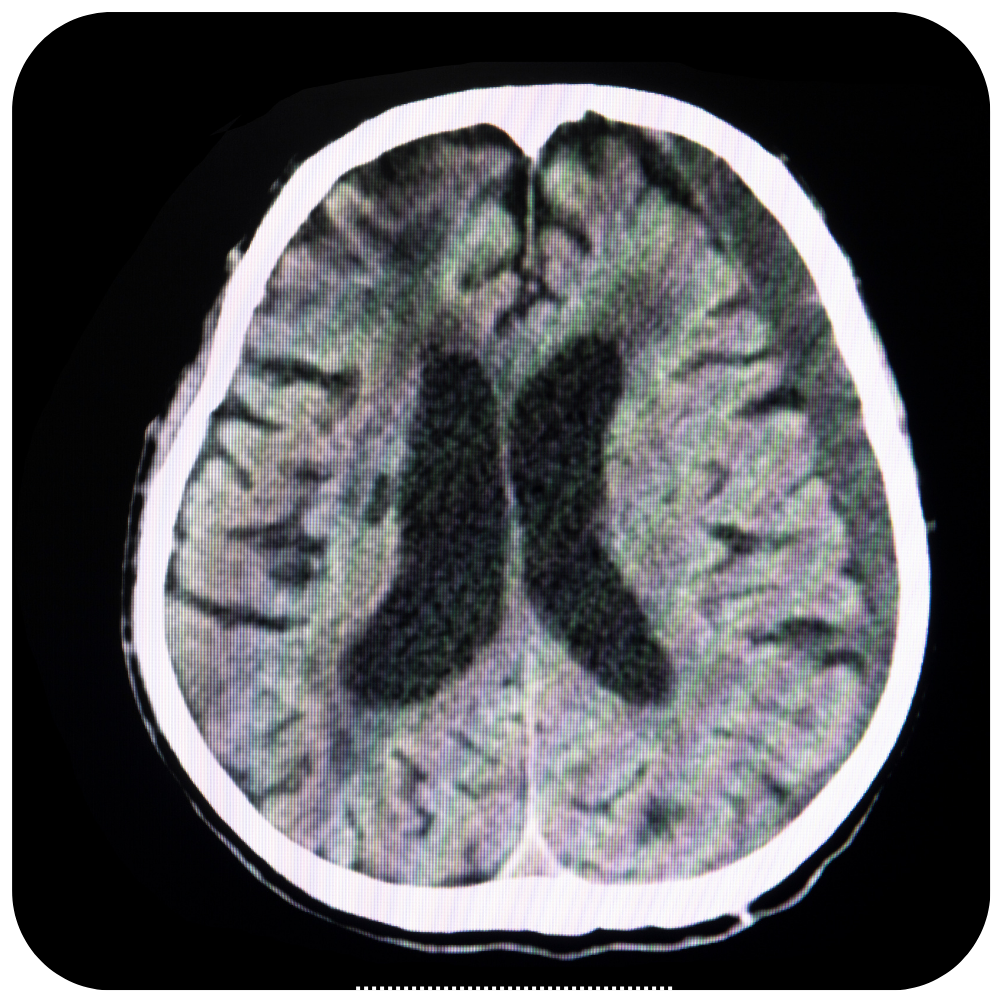

Craneotomía Operación en la que se extrae un pedazo del cráneo. Una craneotomía se realiza para que los médicos puedan extraer un tumor o tejido anormal del cerebro. También se puede realizar para extraer sangre o coágulos del cerebro, aliviar la presión en el cerebro después de una lesión o…